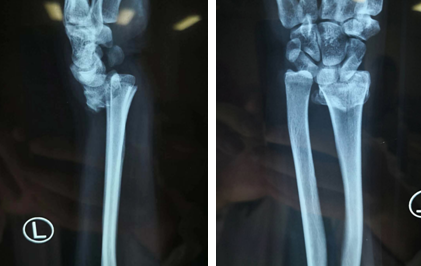

2018年12月,呼呼的北风吹得人直打寒颤,一位女士来到betway在线登陆手外科二病区,找到齐伟亚主任。她说天冷路滑,自己不小心跟人撞车了,万幸伤得不太严重,只是手骨折了,请齐主任帮她看看。齐主任看了看她的手腕背部高高隆起的地方,猜测“桡骨远端骨折”。

经过专科检查,发现女士左手桡骨远端骨折,骨头塌陷。齐主任说:“车祸造成桡骨远端骨折的情况非常常见,不少患者都来找过我。做个腕关节镜手术吧,恢复效果还可以。”女士面露难色,“齐主任,做手术能恢复到正常水平吗?不瞒您说,我平时喜欢跳舞,经常参加一些文艺汇演。如果恢复不好,我还怎么跳舞呀?”齐主任说道:“试试看吧,问题应该不大。”